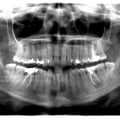

Пацієнтка А. (10 років). Первинна адентія внаслідок вродженої ектодермальної дисплазії